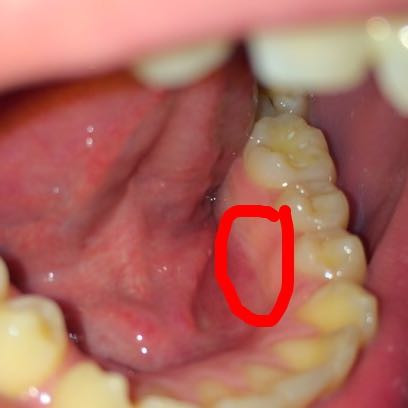

Was Kann Das Sein Mit Einem Bild Zunge Speichel